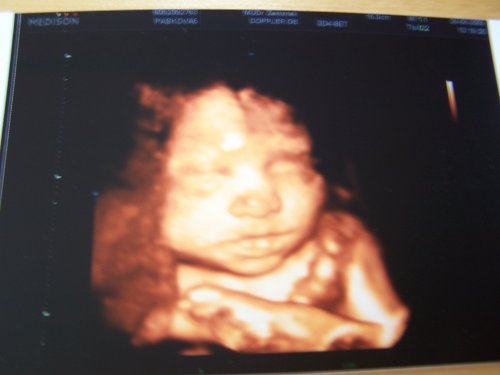

Anetka, naše první štěstíčko 🙂